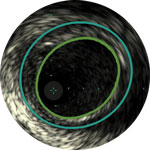

Guides device sizing to ensure precise wall apposition, drug delivery, and placement

Understand plaque type and severity to help guide proper device selection

Visualize plaque burden location for precise treatment

Confirm true lumen or sub-intimal guidewire location

Using case based examples, Dr Stavroulakis discusses the four pillars of IVUS, a framework that demonstrates the added value IVUS brings to angiography